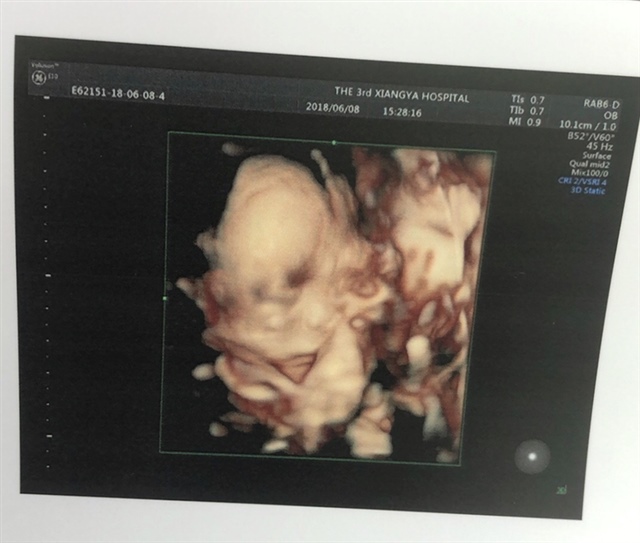

可乐双胞胎兄弟

2018-06-01

2736 人回复